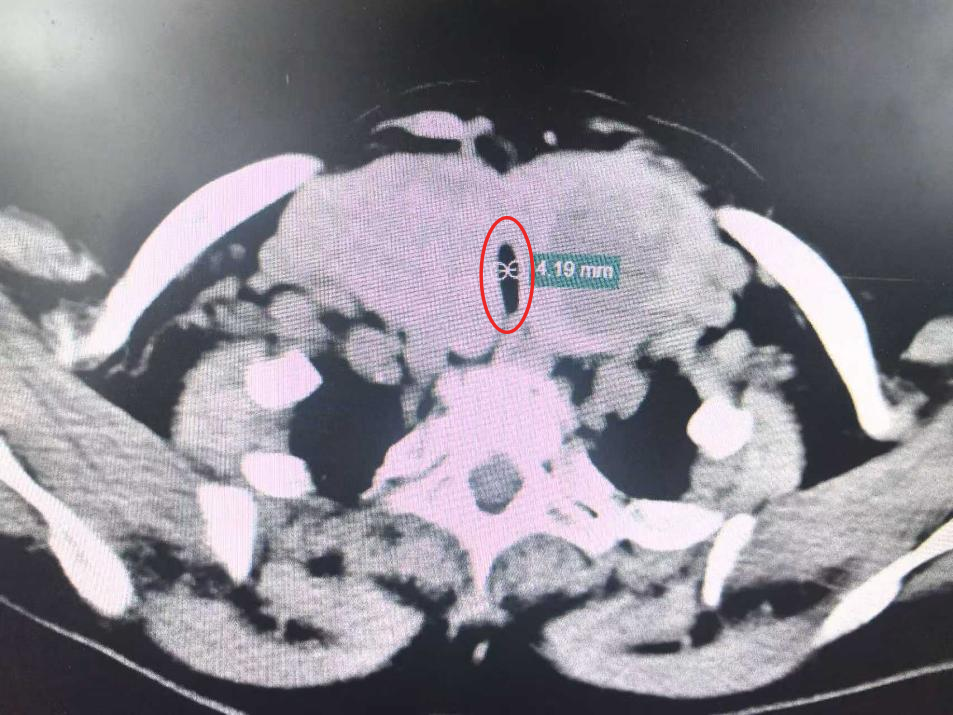

导致婆婆呼吸困难的原因是一处巨大胸骨后甲状腺肿,肿块最大直径超过了 10 厘米。双侧巨大甲状腺压迫着气管,导致气管仅剩「一线天」,最窄处仅 4.1 毫米。更要命的是,肿块顺着胸廓入口向胸腔蔓延,最低处紧邻主动脉弓,就像一颗「不定时炸弹」悬在胸腔内;而颈段甲状腺肿块则向两边横向发展,压迫着颈动脉鞘。如果任由肿块继续生长,或者任何轻微的痰液堵塞,都可能让婆婆瞬间窒息。